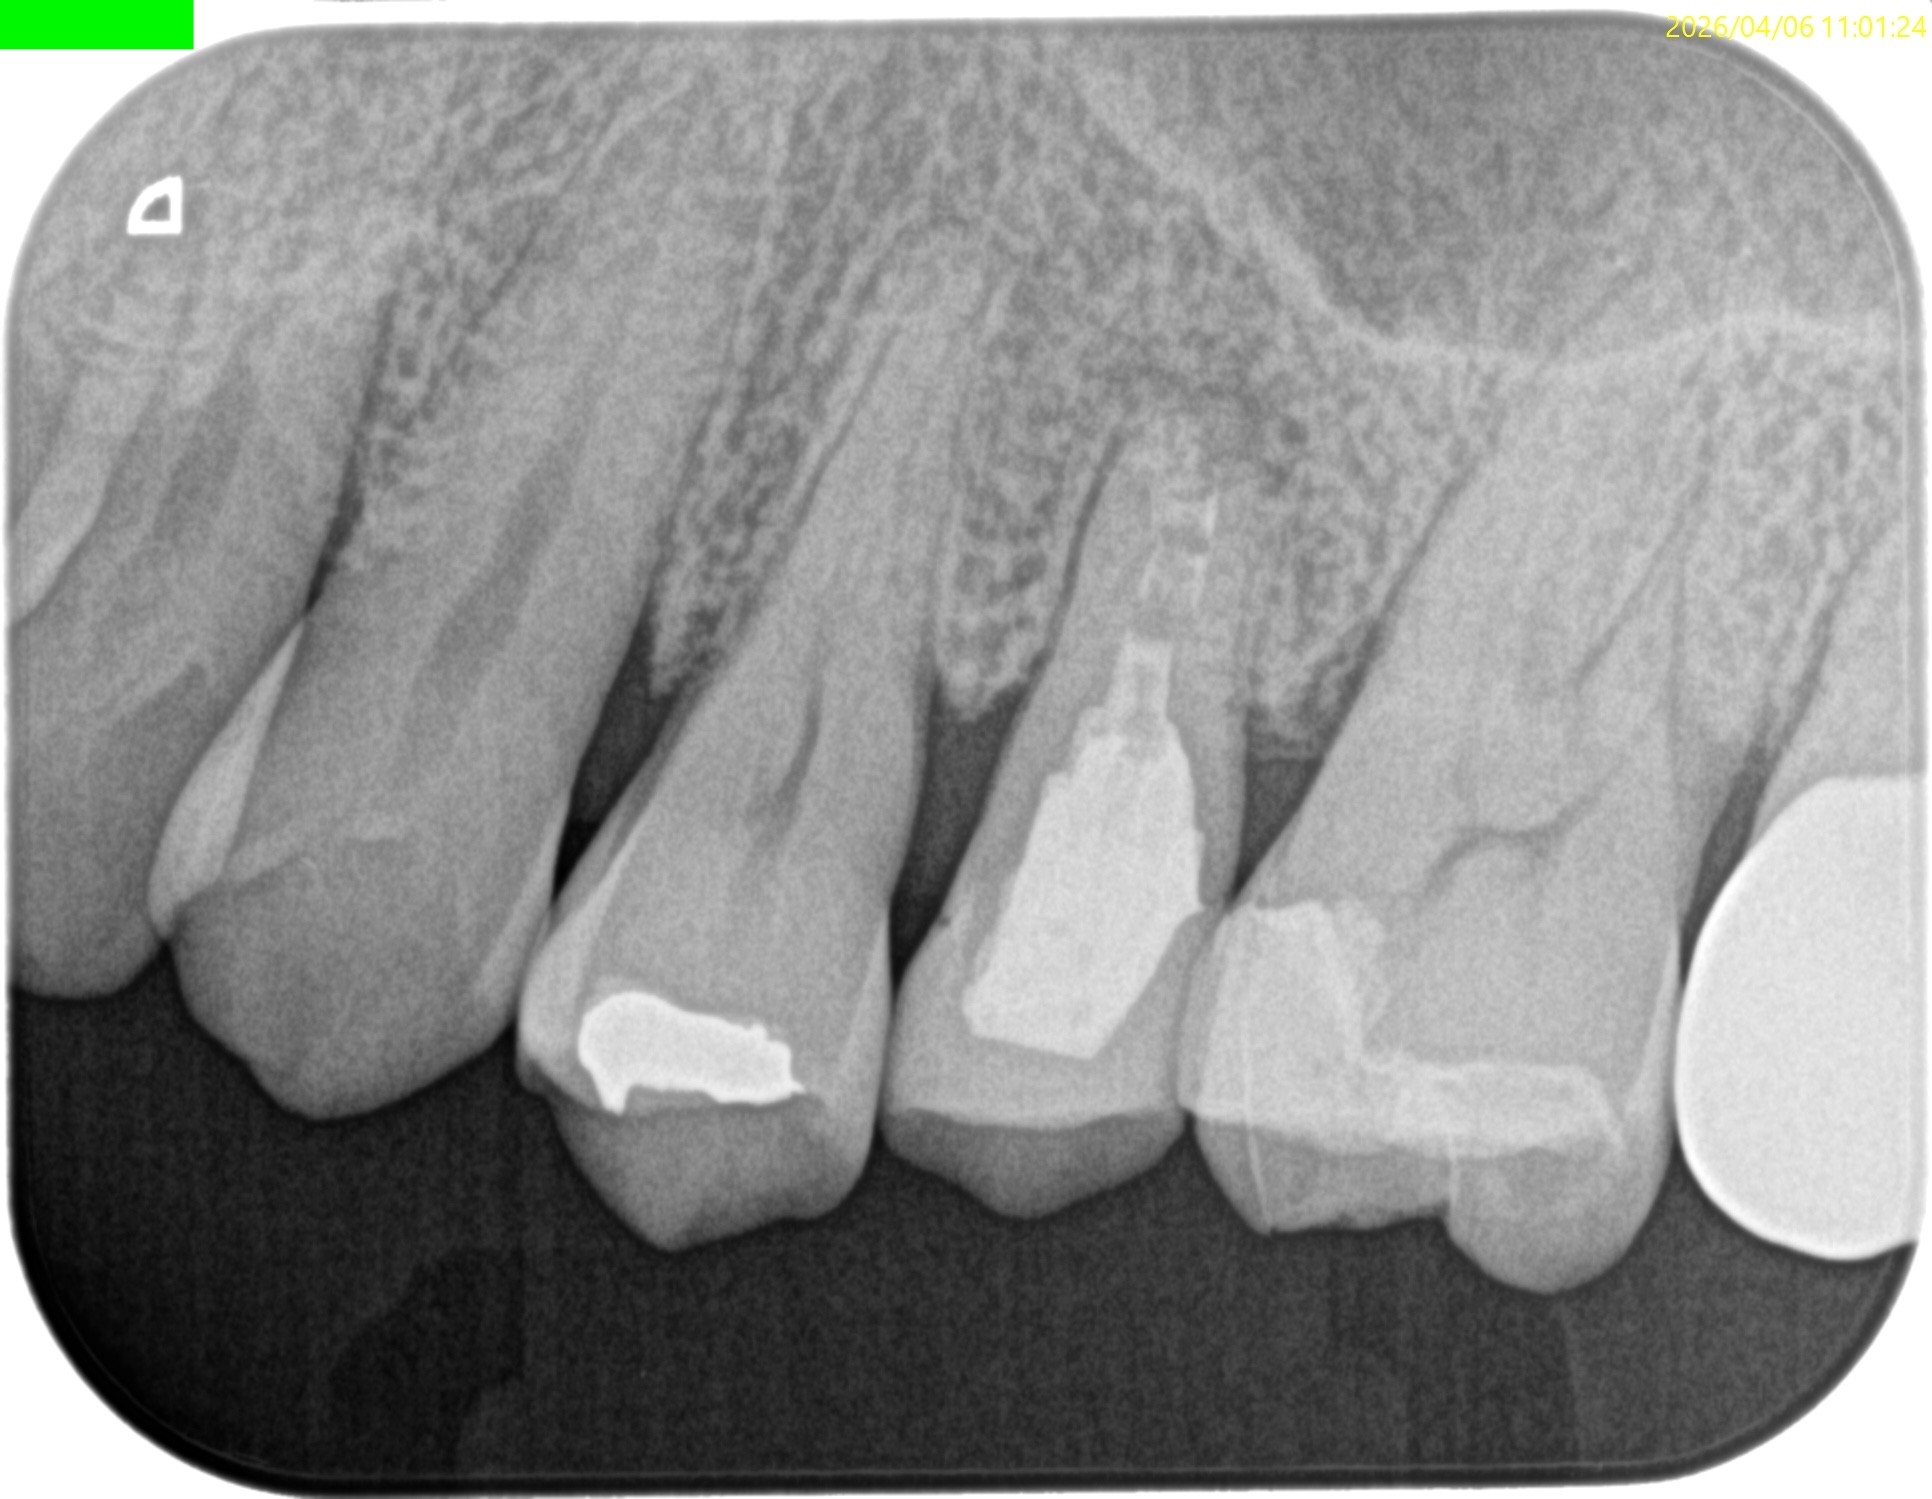

Pre-op Endo test(2026.4.6)

臨床症状はないが…

上顎洞炎は治癒したままだが、Lid TechniqueのLidごと材料が外れてしまっている。